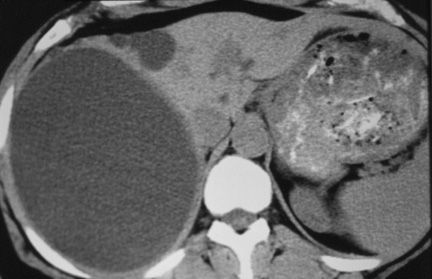

Nang sán chó (Hydatid cyst) ở gan với hình ảnh nang mẹ vá các nang con